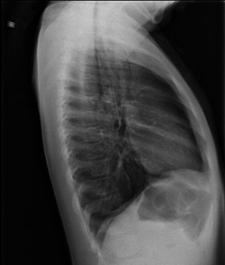

TRAUMATISME TORACICE

Emfizem subcutanat

Emfizem subcutanat Emfizem subcutanat

Aspect radiologic Imagine CT

Pneumotorace sufocant bilateral Pneumotorace sufocant stang

Hemo-pneumotorace stangDetaliu Fracturi costale multiple.Volet costal drept

Fracturi costale multiple Hemitorace drept strivit

Volet costal si hemotorace

drept Fracturi costale multiple

Volet costal si hemotorace drept

Hemitorace drept strivit Hemitorace drept strivit Hemitorace drept strivit